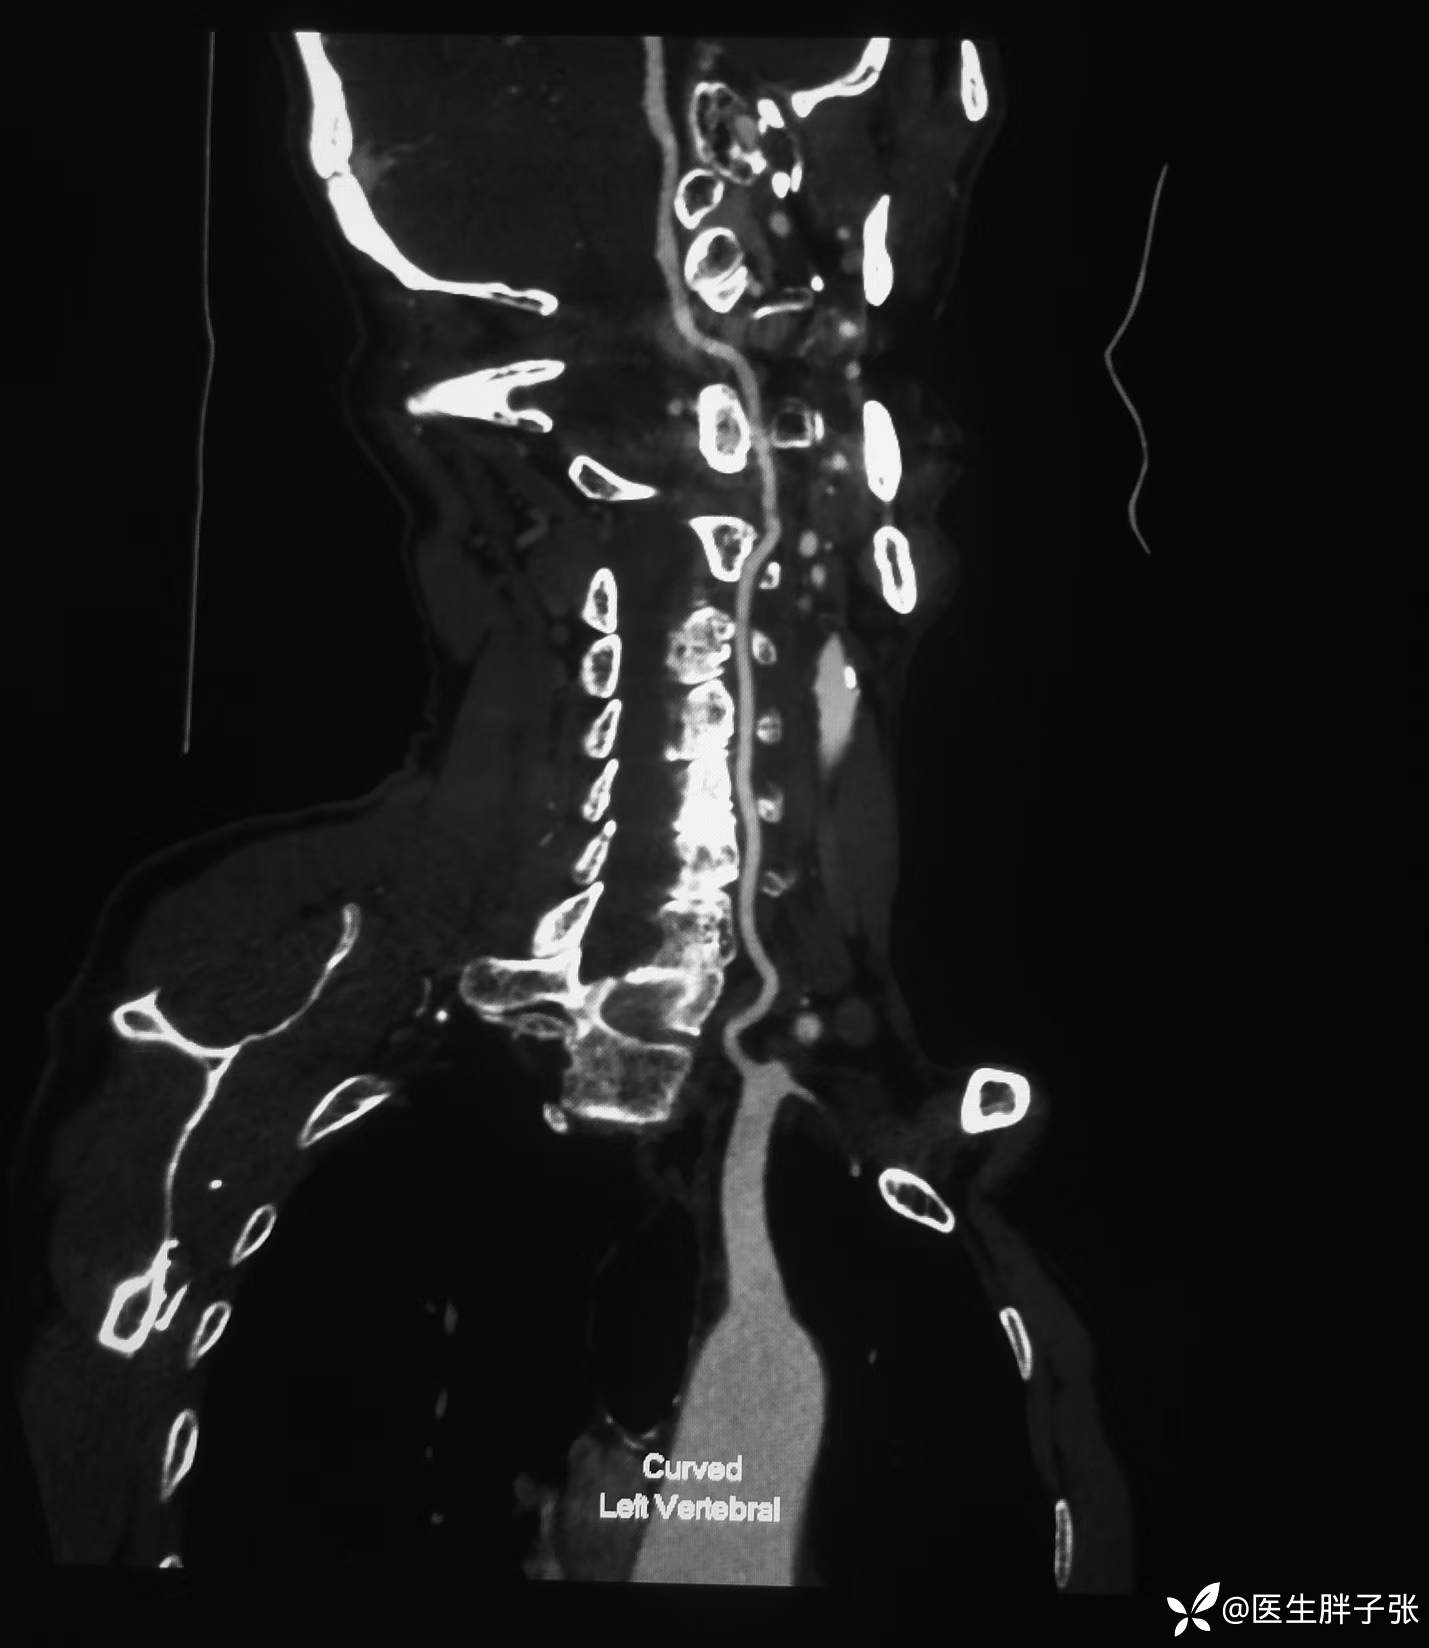

头颈部CTA